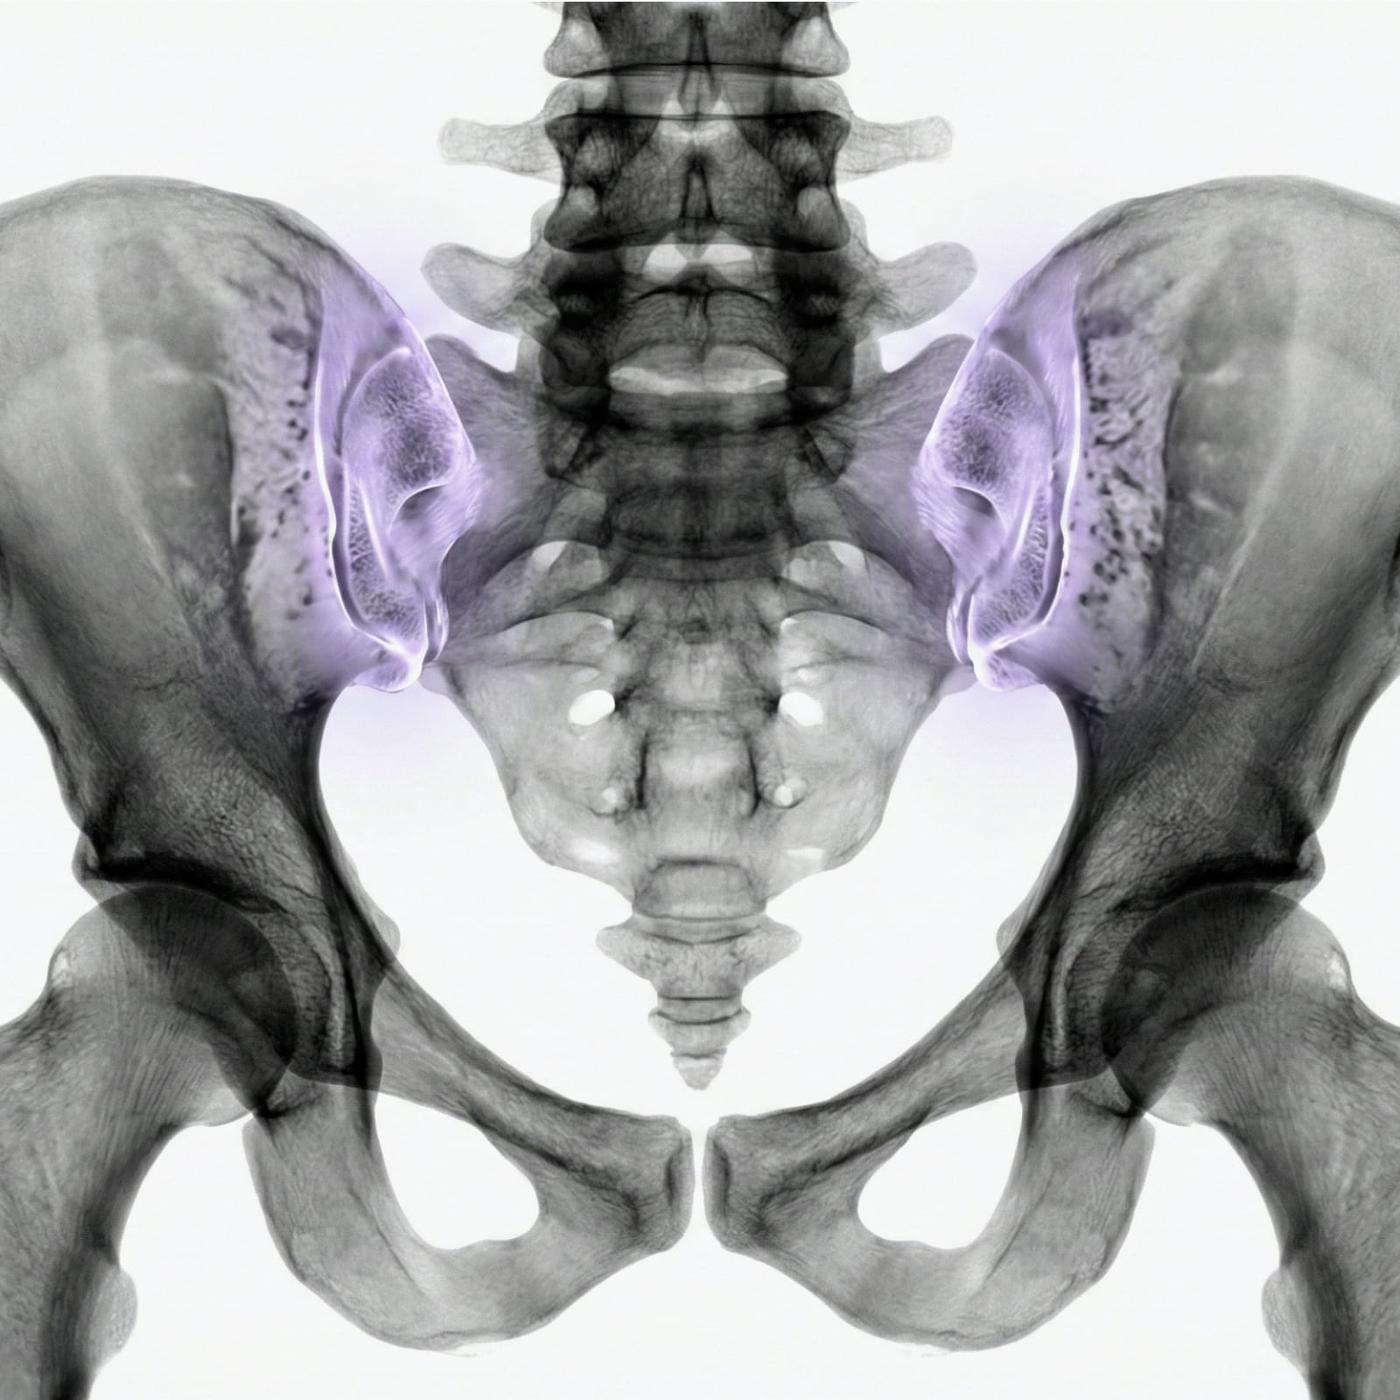

MR av bäckenet och höftleden ger högupplösta bilder av skelett, ledbrosk, senor, slemsäckar och omkringliggande mjukdelar – helt utan strålning. Undersökningen är helt smärtfri och kan identifiera allt från tidiga artrosförändringar till inflammationer eller vävnadsskador.

En MR av höft eller bäcken är ett kraftfullt diagnostiskt verktyg som ger detaljerad information om skelett, ledytor, senor, brosk, slemsäckar och omgivande vävnader.